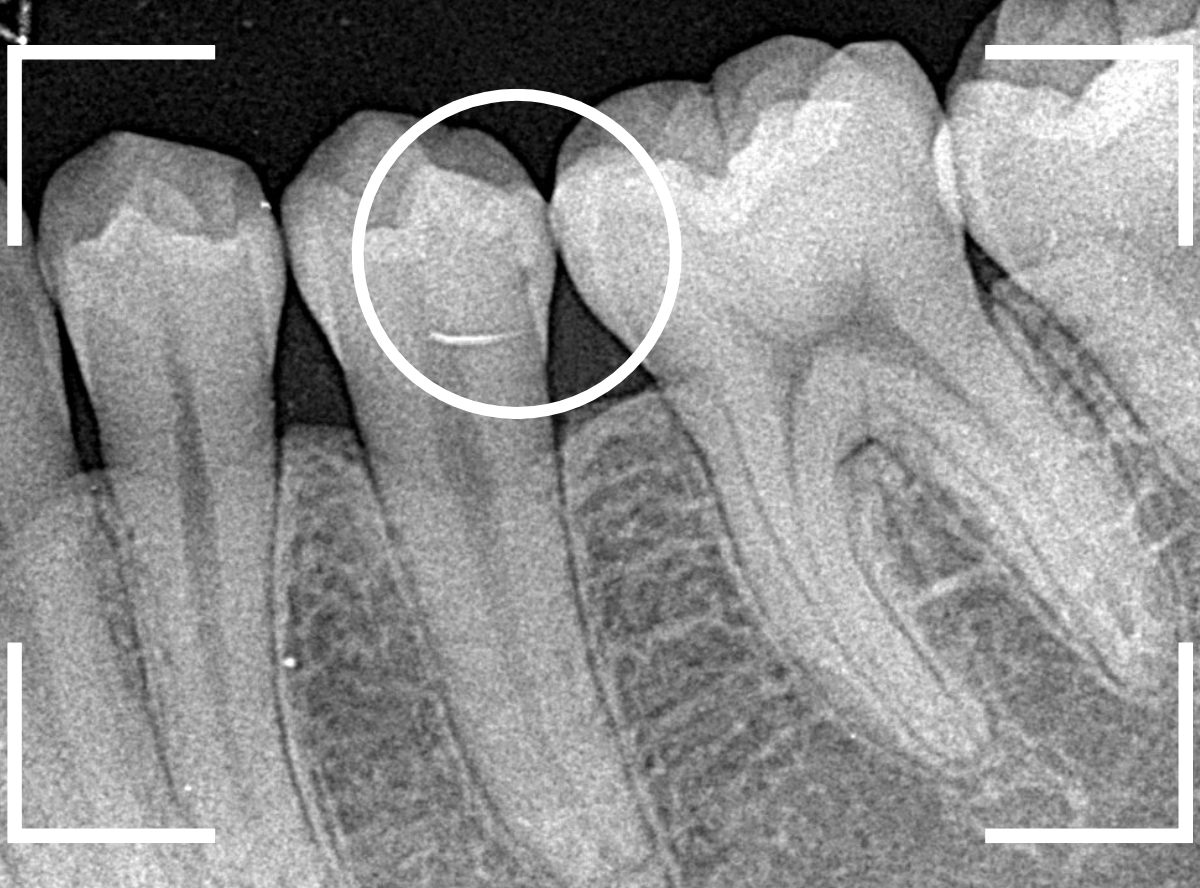

Case.25 深い虫歯の治療~無事にセラミック・インレーへ

今回は、上の奥歯が深くて広い虫歯になっていた方のケースです。

〇部が虫歯の部分です。

この写真からは深い虫歯があるのは想像つきません。

レントゲン写真で確認します。

青い線が神経、赤い線が虫歯の部分です。

前後の歯とも、かなり深く広い虫歯になっているのがわかります。